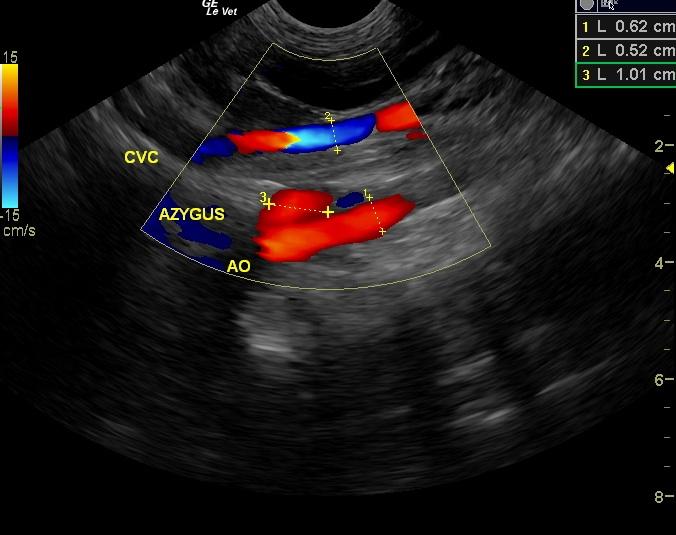

A 4-year-old F Yorkshire Terrier dog was presented at an emergency facility for acute onset disorientation, unresponsiveness, and vomiting. On physical examination, she appeared blind and was disoriented. Abnormalities on CBC and blood chemistry were low MCV and hypocholesterolemia. The patient was treated with K/D diet. Recheck blood work a month later showed alkaline phosphatase normalized and a normal WBC. Eight months later, the owner reported that the patient was still vomiting 1-2 times a week and getting Lactulose. CBC showed low MCV and MCHC.

A 4-year-old F Yorkshire Terrier dog was presented at an emergency facility for acute onset disorientation, unresponsiveness, and vomiting. On physical examination, she appeared blind and was disoriented. Abnormalities on CBC and blood chemistry were low MCV and hypocholesterolemia. The patient was treated with K/D diet. Recheck blood work a month later showed alkaline phosphatase normalized and a normal WBC. Eight months later, the owner reported that the patient was still vomiting 1-2 times a week and getting Lactulose. CBC showed low MCV and MCHC. The only change on blood chemistry was elevated ALP activity. Nutrical was added to the therapy. Two weeks later, the patient was presented for vomiting. On physical examination, the patient was febrile and slightly disoriented. The patient was treated with metronidazole and L/D diet. The following morning the owner reported that the patient was back to normal.